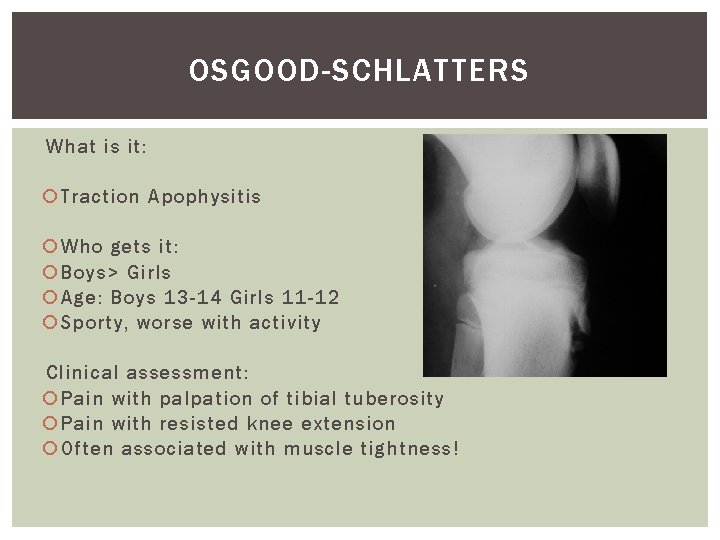

OSGOOD-SCHLATTERS What is it: Traction Apophysitis Who gets it: Boys> Girls Age: Boys 13 -14 Girls 11 -12 Sporty, worse with activity Clinical assessment: Pain with palpation of tibial tuberosity Pain with resisted knee extension Often associated with muscle tightness!